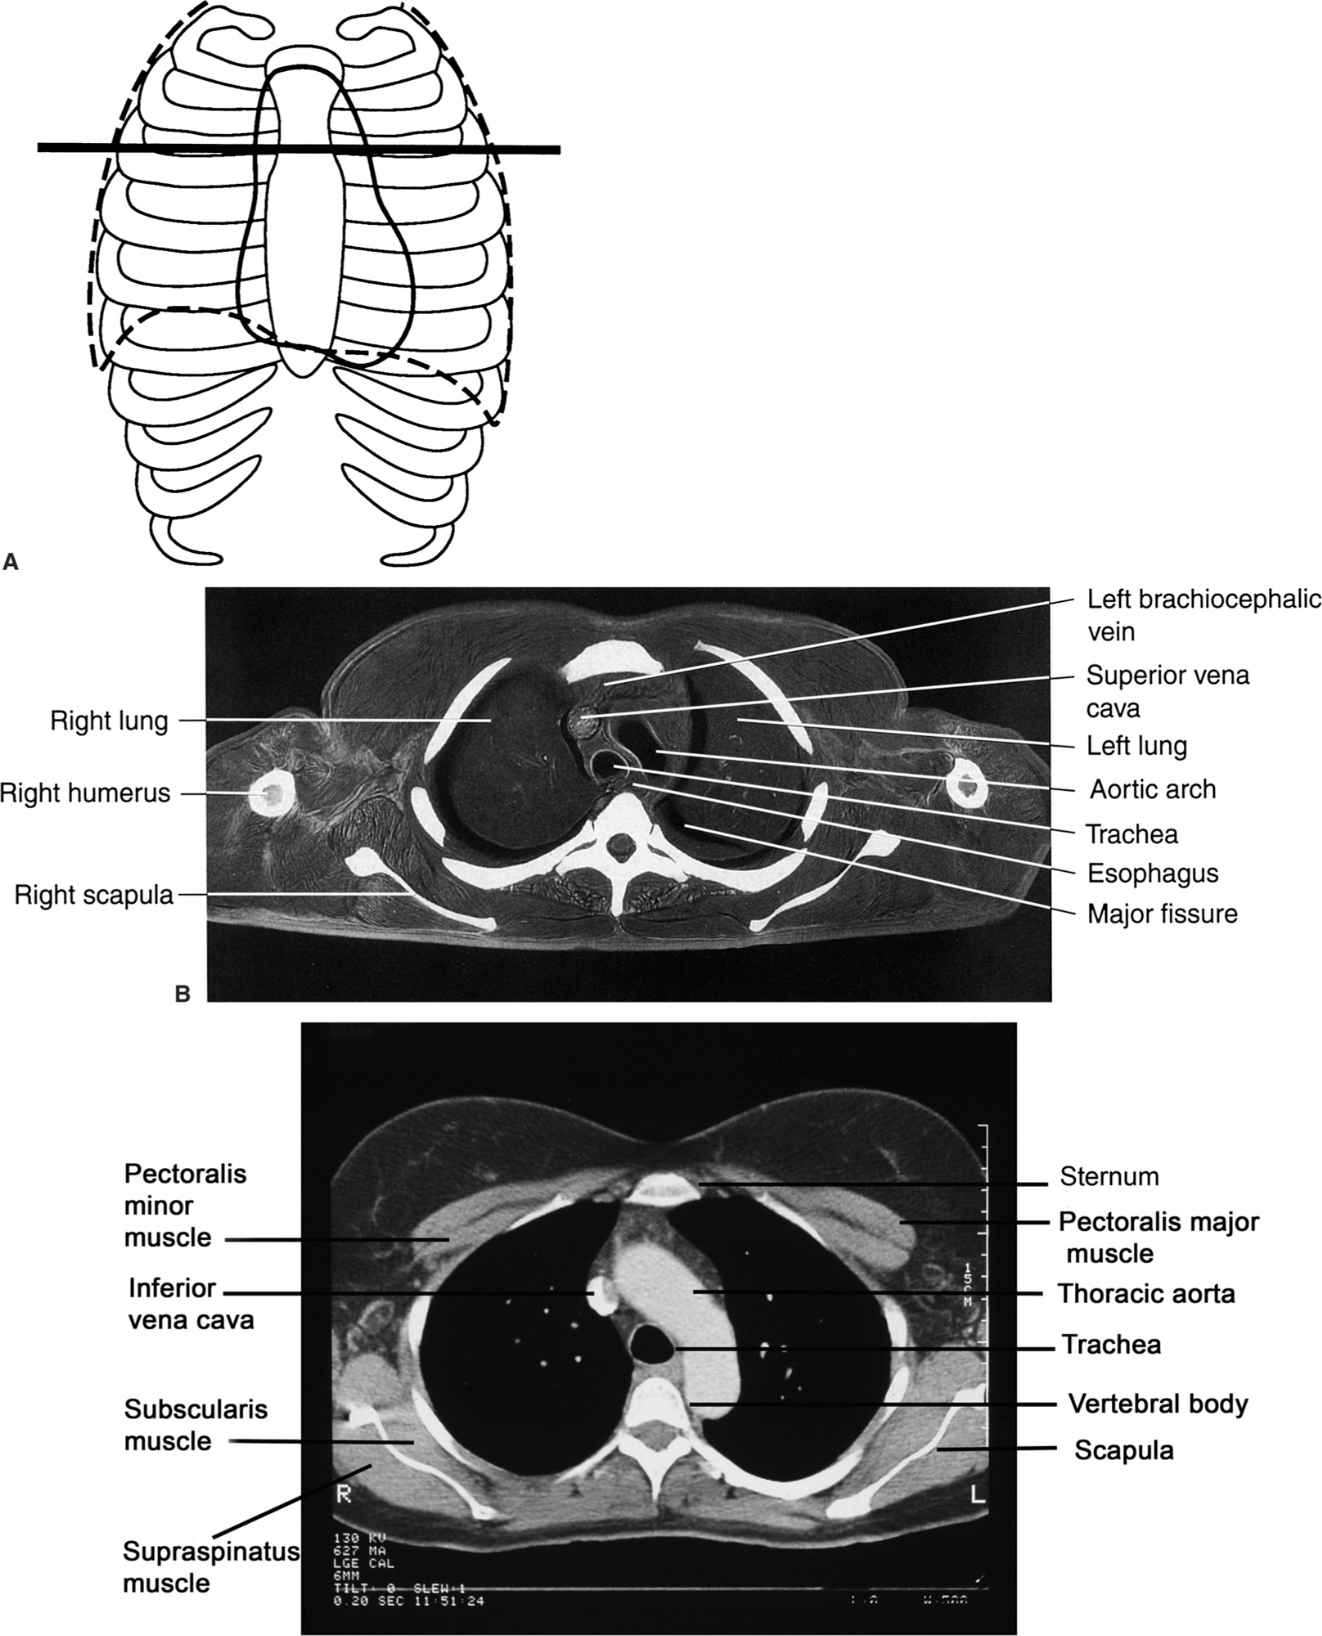

Labeled Chest CT Scan Anatomy